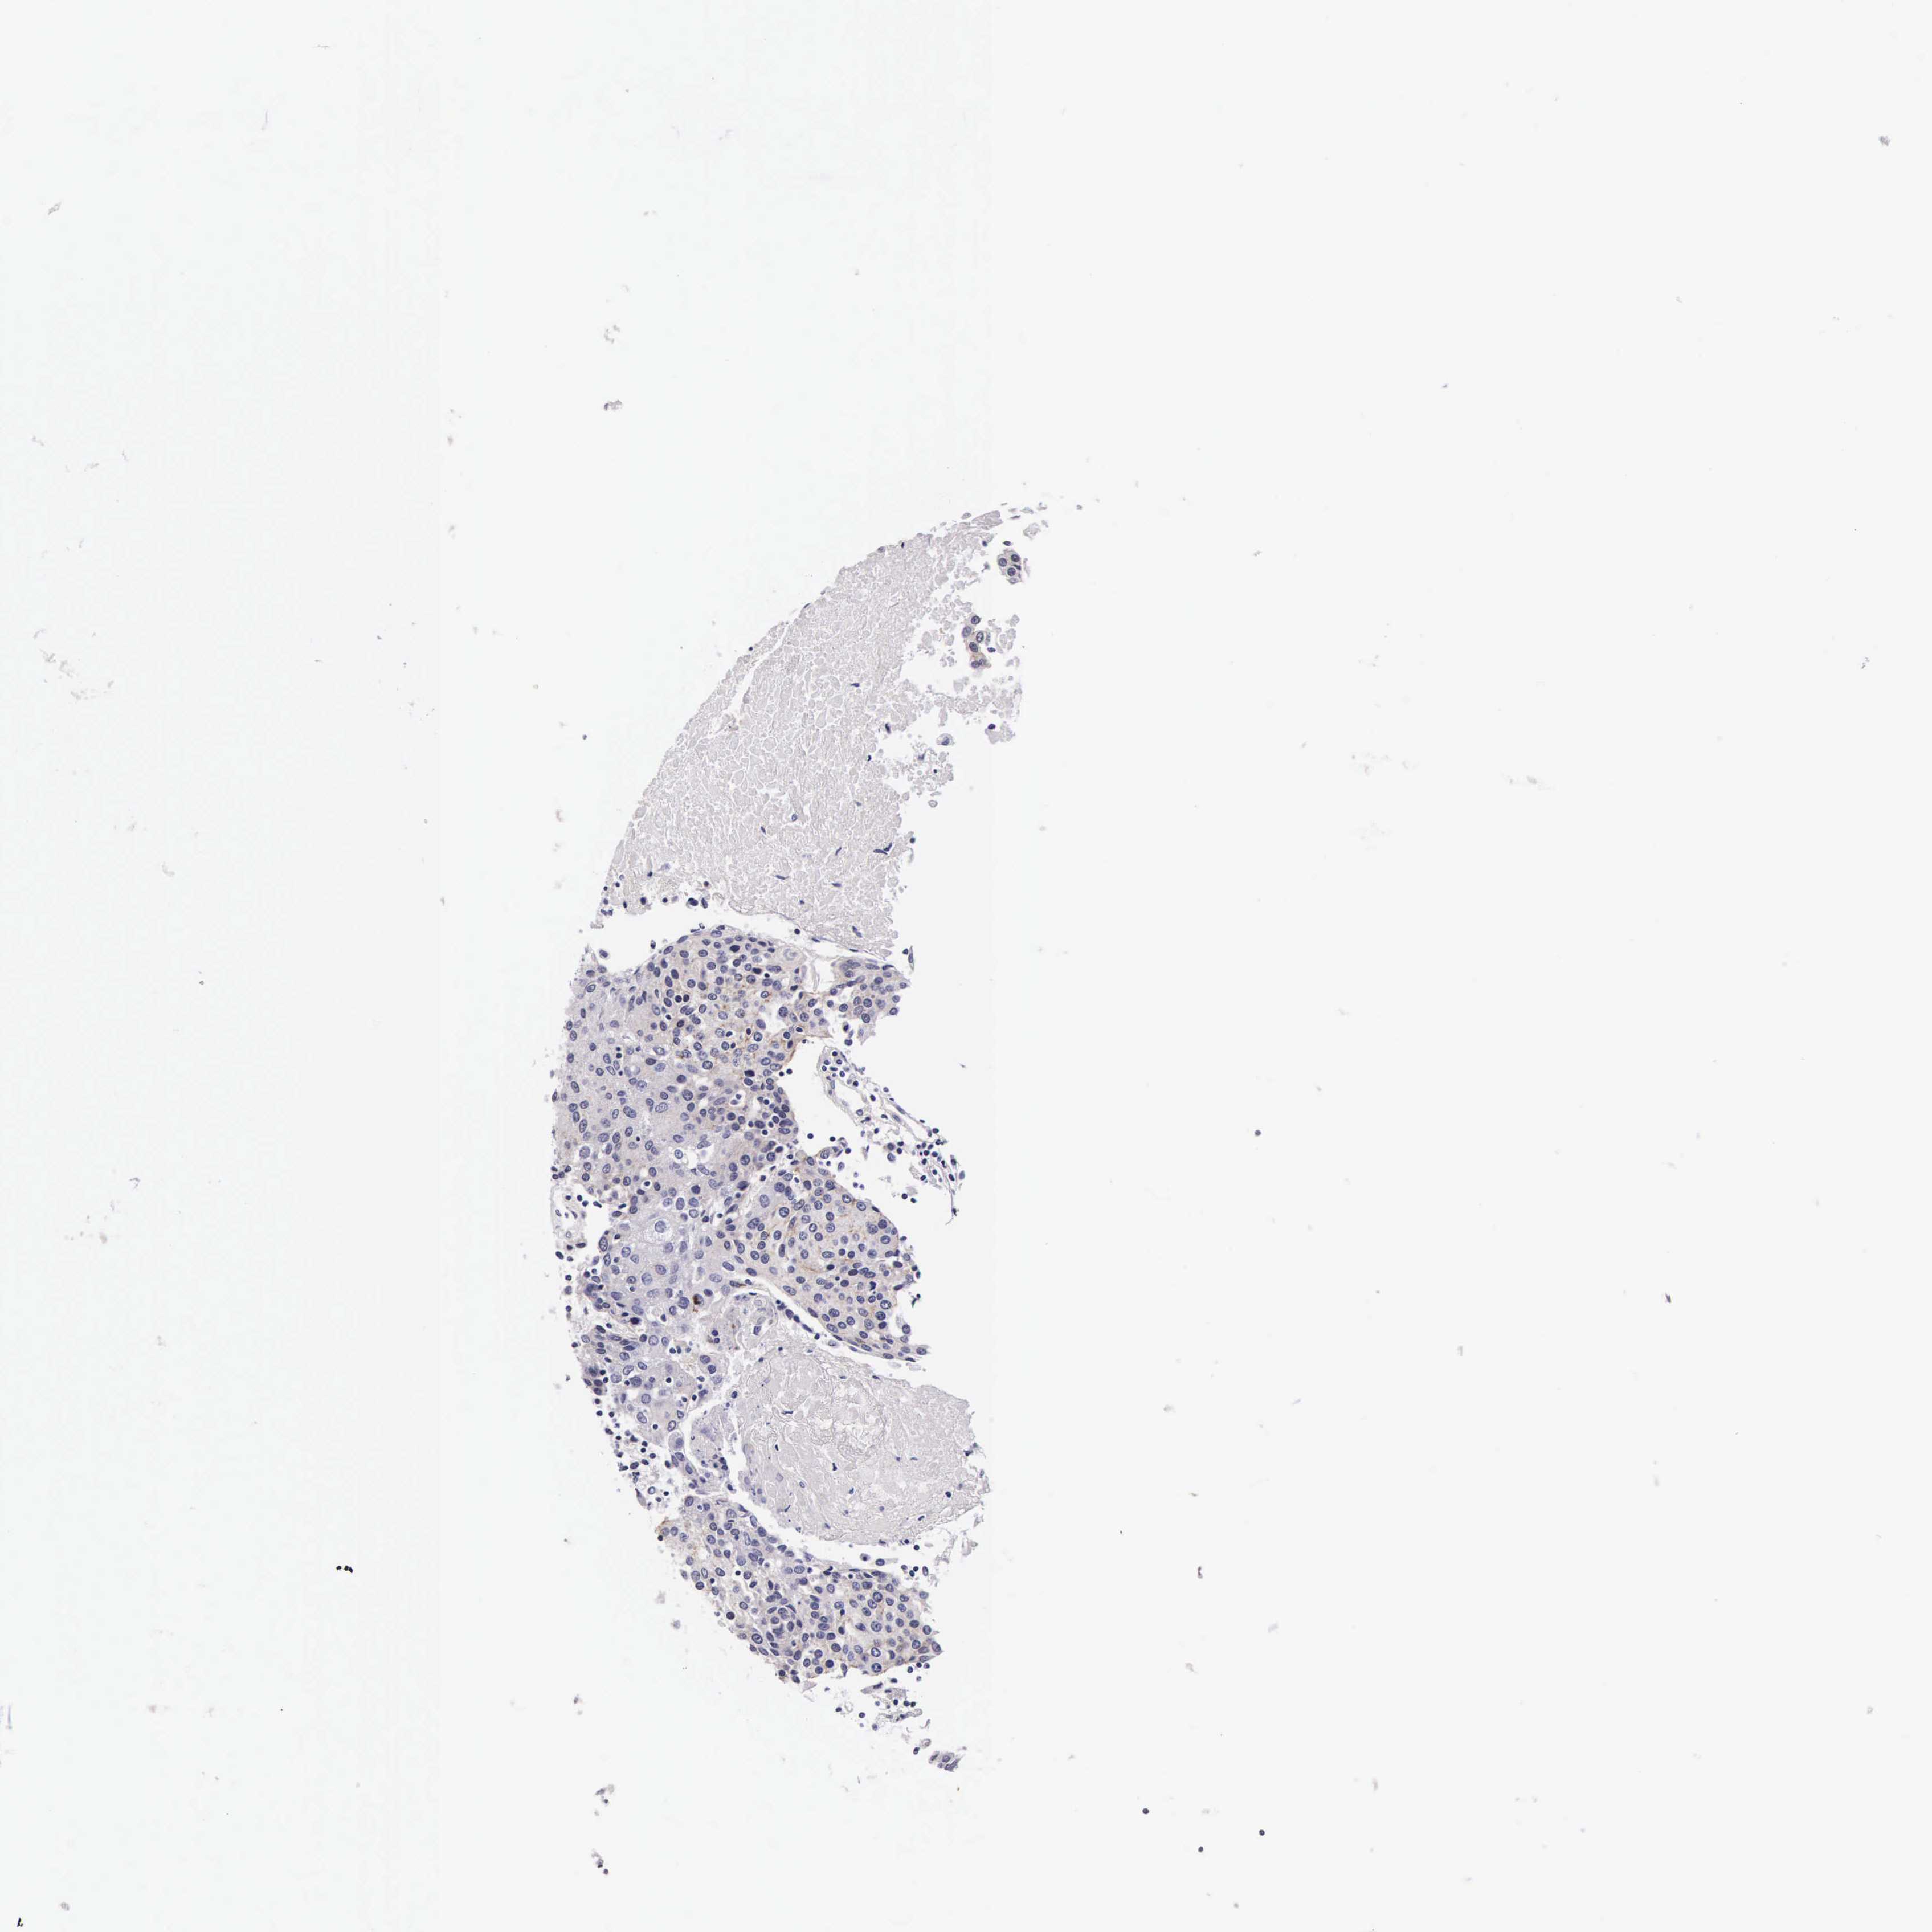

UROTHELIAL CANCER - Protein expressioni

A mouse-over function shows sample information and annotation data. Click on an image to view it in a full screen mode. Samples can be filtered based on level of antibody staining by selecting one or several of the following categories: high, medium, low and not detected. The assay and annotation is described here.

Note that samples used for immunohistochemistry by the Human Protein Atlas do not correspond to samples in the TCGA dataset.

Antibody stainingi

Antibody staining in the annotated cell types in the current human tissue is reported as not detected, low, medium, or high, based on conventional immunohistochemistry profiling in selected tissues. This score is based on the combination of the staining intensity and fraction of stained cells.

Each image is clickable and will lead to virtual microscopy that enables deeper exploration of all samples and also displays staining intensity scores, fraction scores and subcellular localization as well as patient and tissue information for each sample.

Antibody HPA000647

Staining

High

Medium

Low

Not detected

Intensity

Strong

Moderate

Weak

Negative

Quantity

>75%

75%-25%

<25%

None

Location

Nuclear

Cytoplasmic/membranous

Cytoplasmic/membranous,nuclear

Urothelial carcinoma, High grade

Urothelial carcinoma, Low grade